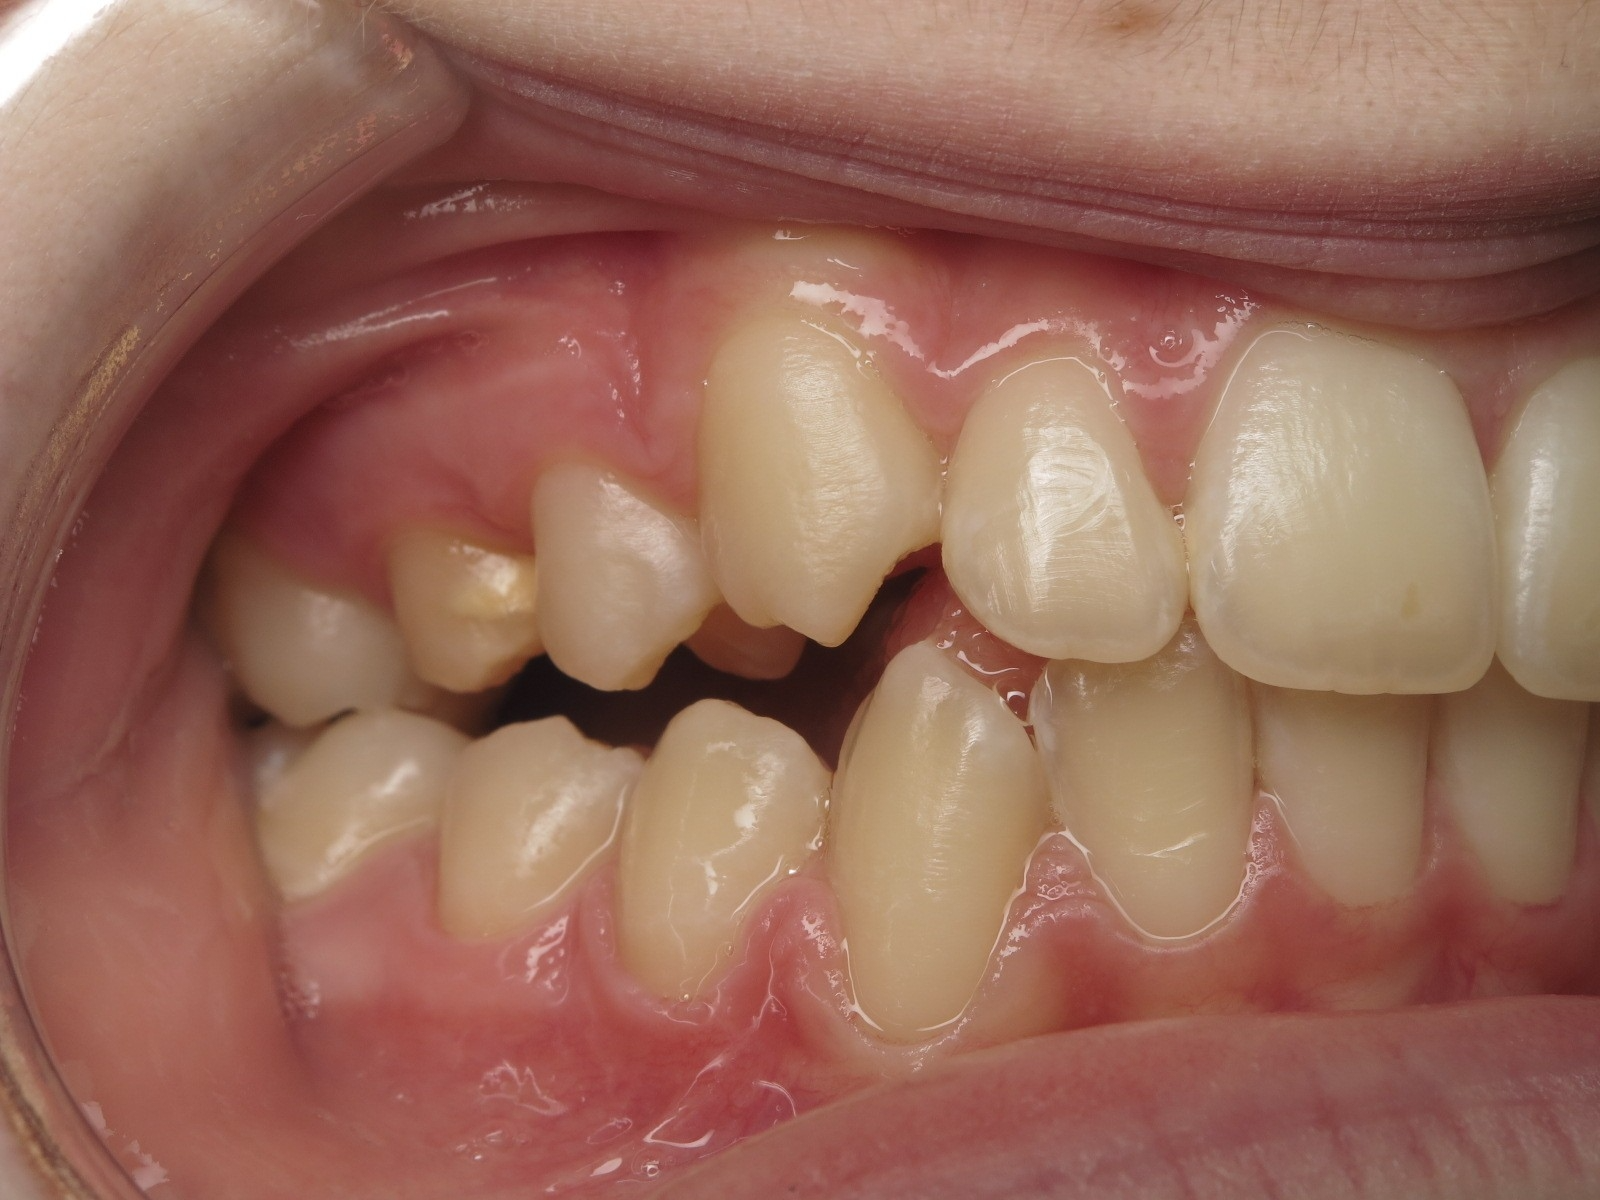

appareillage mobile

sectionnel multibagues